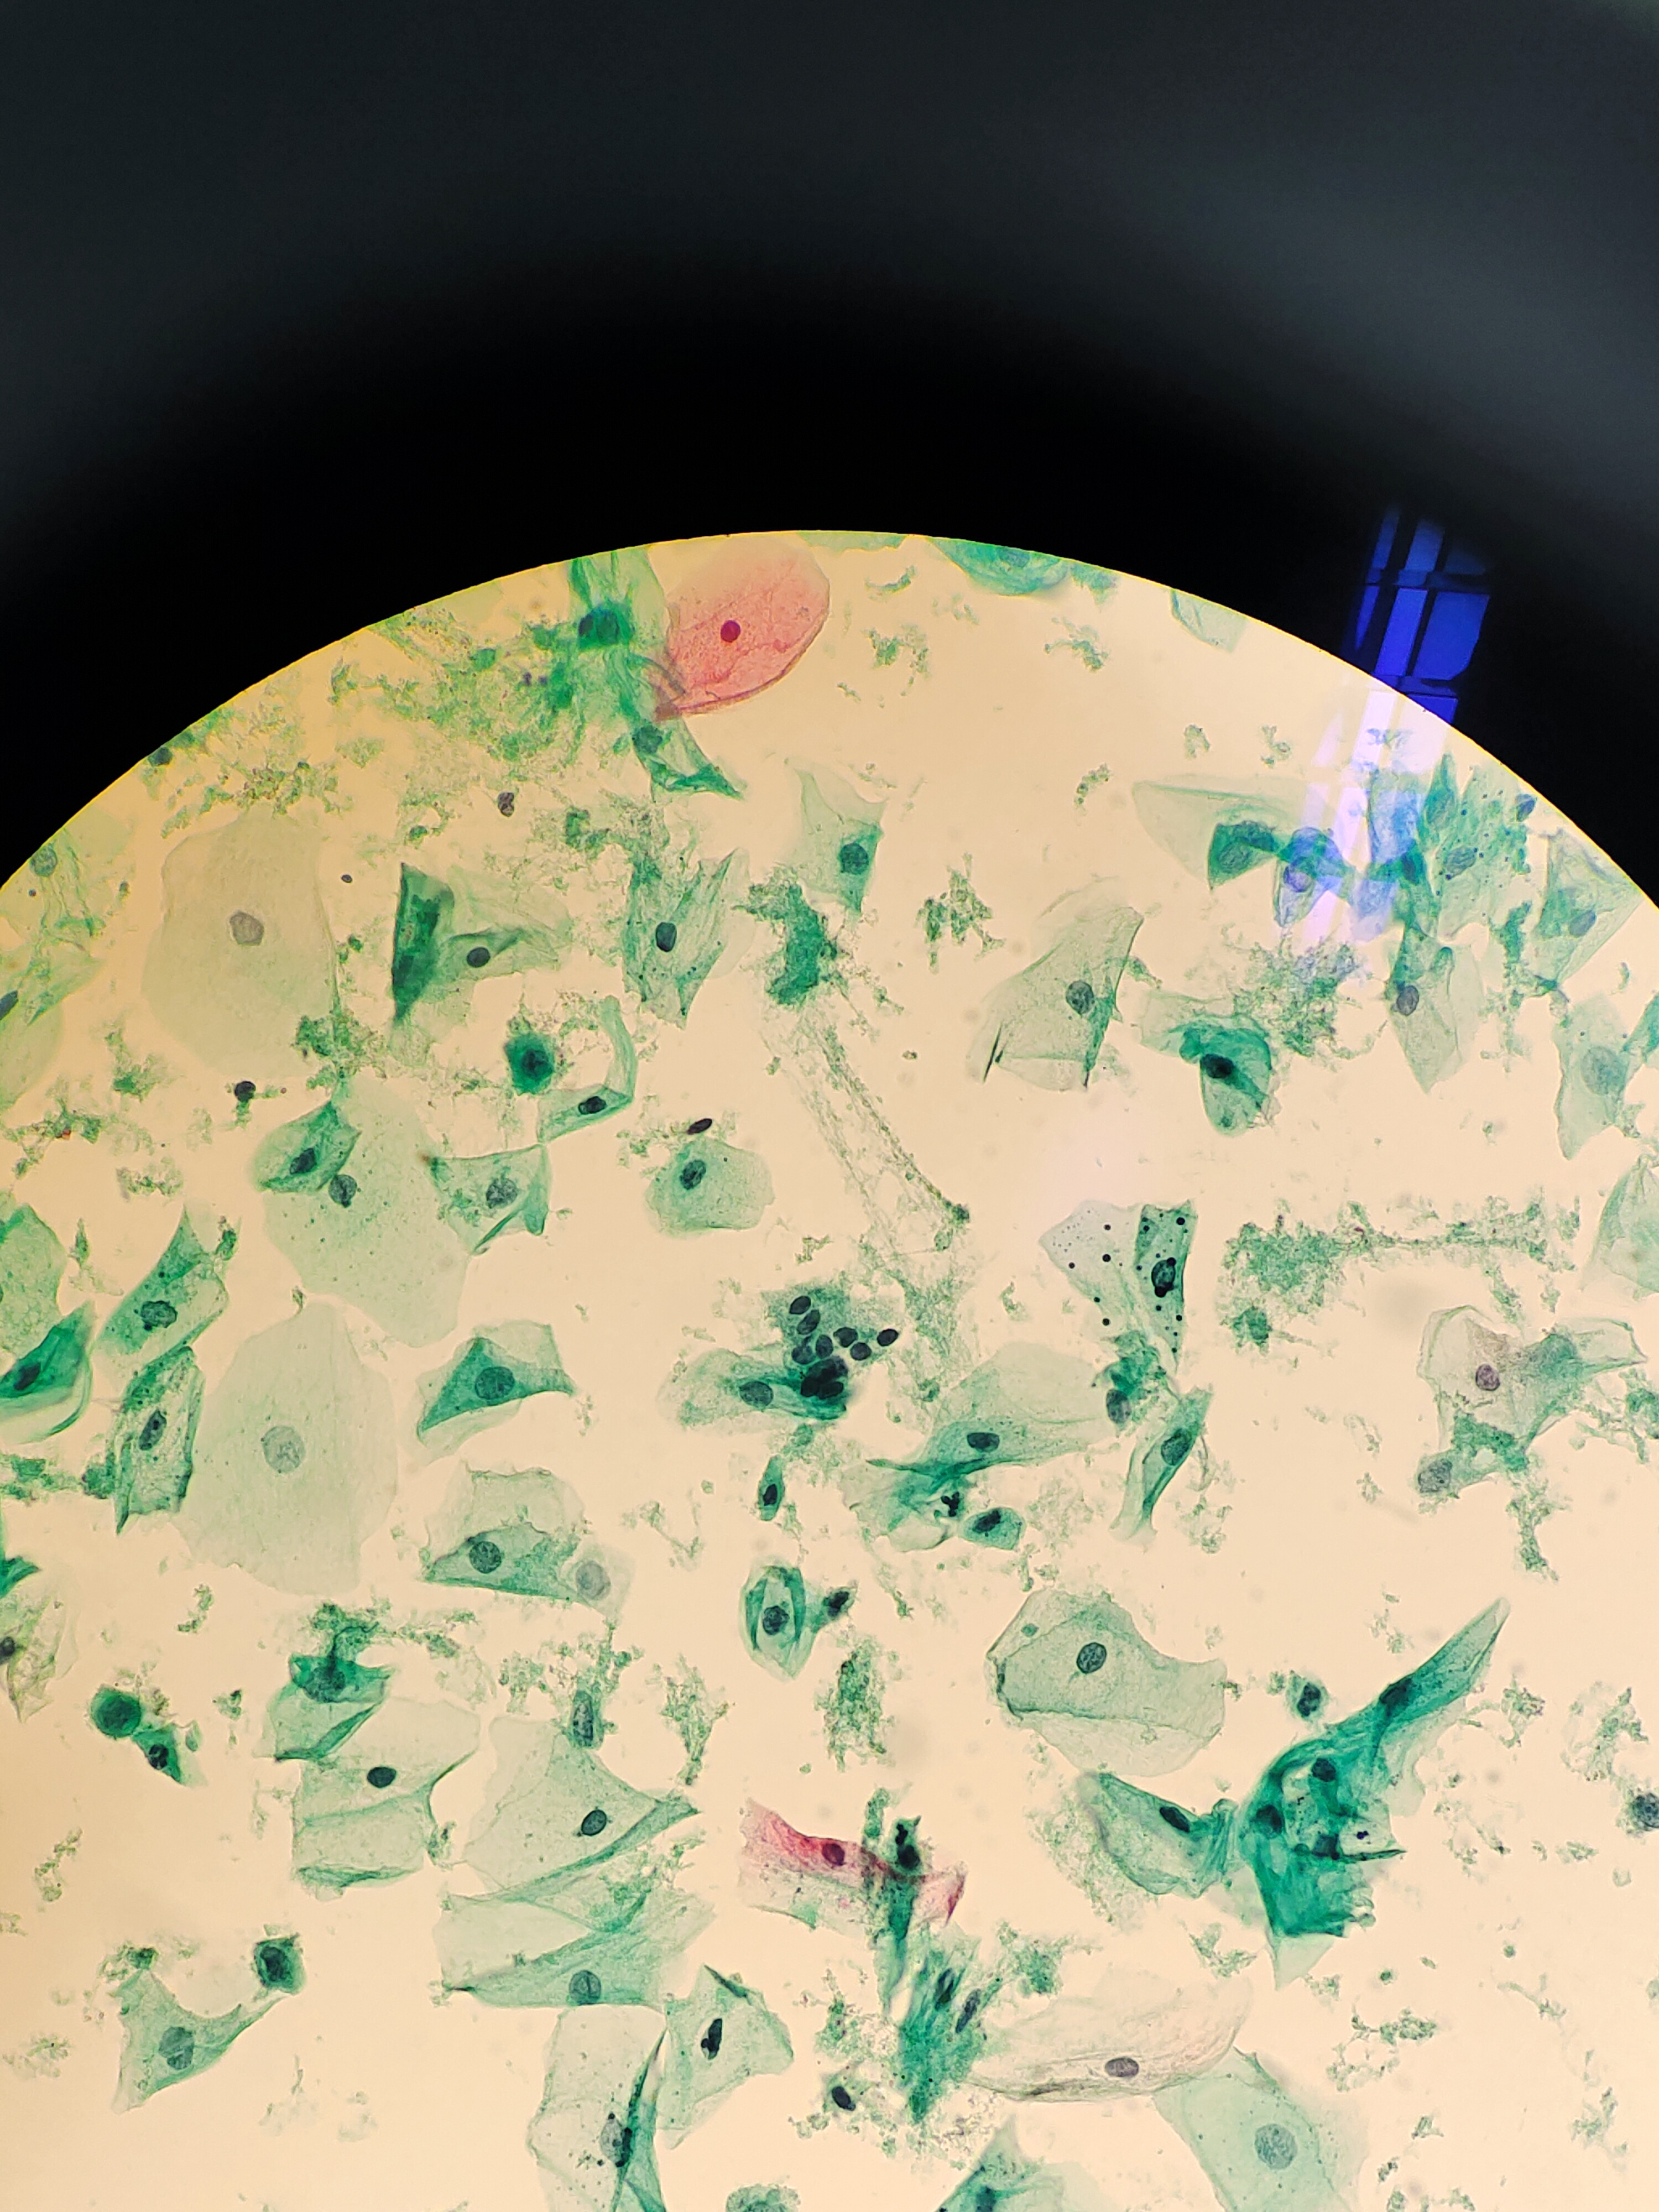

性别

女

年龄

77岁

一般病史

绝经20多年,阴道出血3天。HPV阴性。老师们,细胞不萎缩,有些核深染细胞,有事吗?

标本类型

宫颈

制片方法

液基

染色方法

巴氏

图1